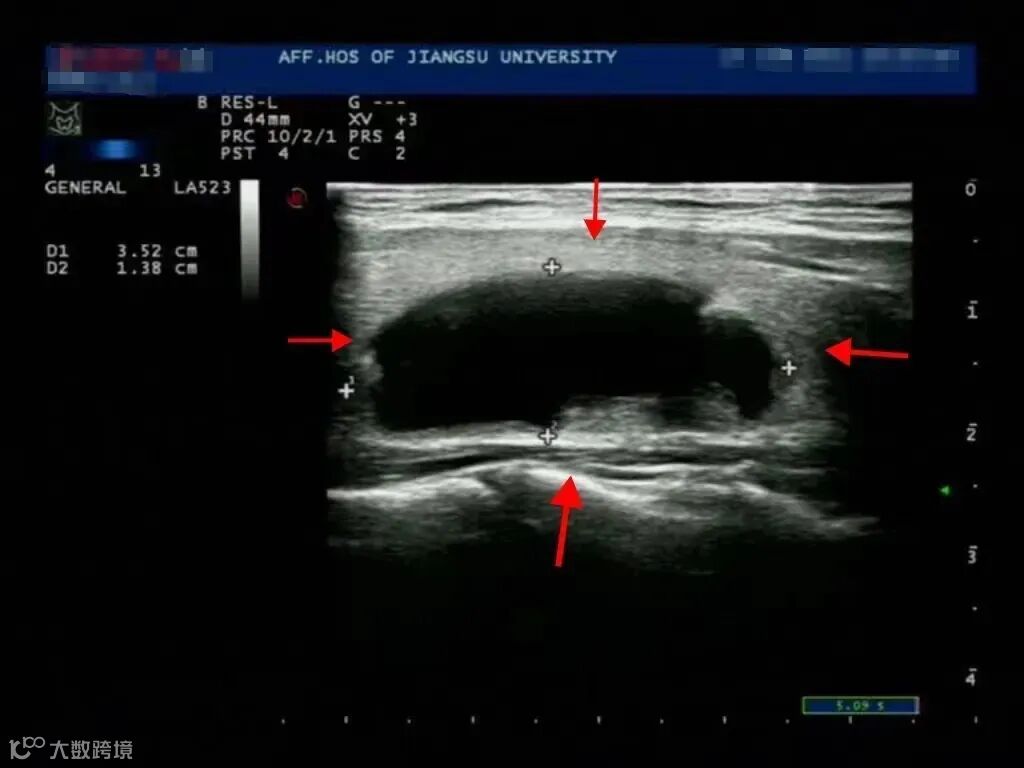

肝胆腺体外科主任医师刘琛为她进行了仔细的检查,考虑可能是甲状腺结节,建议王女士做个B超看看。超声医生把探头往王女士脖子上一放,果然,王女士的甲状腺上长了一个3.5厘米的结节。

这个3.5厘米的结节实在是影响美观,传统的手术治疗留下长长一道疤也不好看,这让王女士十分苦恼。有没有什么办法既能消灭这个结节,又不留下疤痕影响美观呢?有的!医生告诉王女士,微波消融治疗可以同时满足她这两个要求。

治疗前